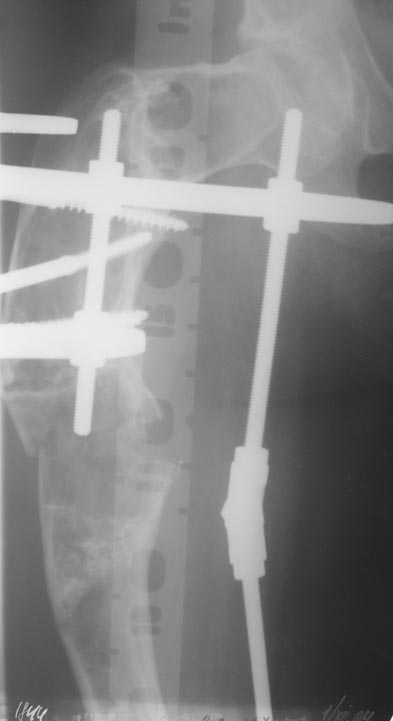

Уважаемые коллеги! С Новым годом и самых светлых пожеланий!В ноябре этого года я обращался с просьбой о помощи в выборе тактики лечения больной с деформацией бедра на почве фиброзной дисплазии. Были получены интересные и очень полезные советы по операции.

Хотелось бы показать, что получилось в результате.Операция выполнялась с помощью А.Н.Челнокова. Очень понравилась технология выполнения блокируемого остеосинтеза с использованием спицевого дистрактора, модифицированный гвоздь с латерализованным проксимальным отделом и возможностью многовинтовой фиксации проксимального и дистального участков бедра.

Прекрасная работа, поздравляю Александра и Леонида с удачной реконструкцией: длины и контура бедра.